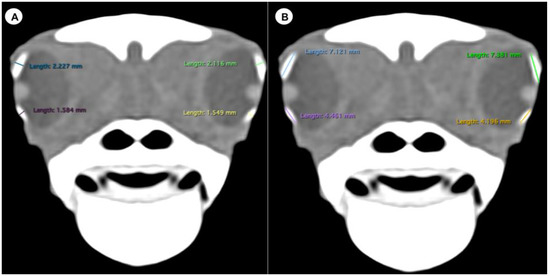

- (A)

- Transverse plane respect to the eyeball

- Lens diameter, understood as the maximum distance between the lateral and medial edges of the lens (equatorial diameter) (Figure 1A).

- Internal diameter of the sclerotic ring, or maximum distance between the inner lateromedial edges of the ring, close to the cornea (Figure 1A).

- External diameter of the sclerotic ring or maximum distance between the outer lateromedial edges of the ring, close to the sclera (Figure 1A).

- (B)

- Transverse plane concerning the turtle’s body